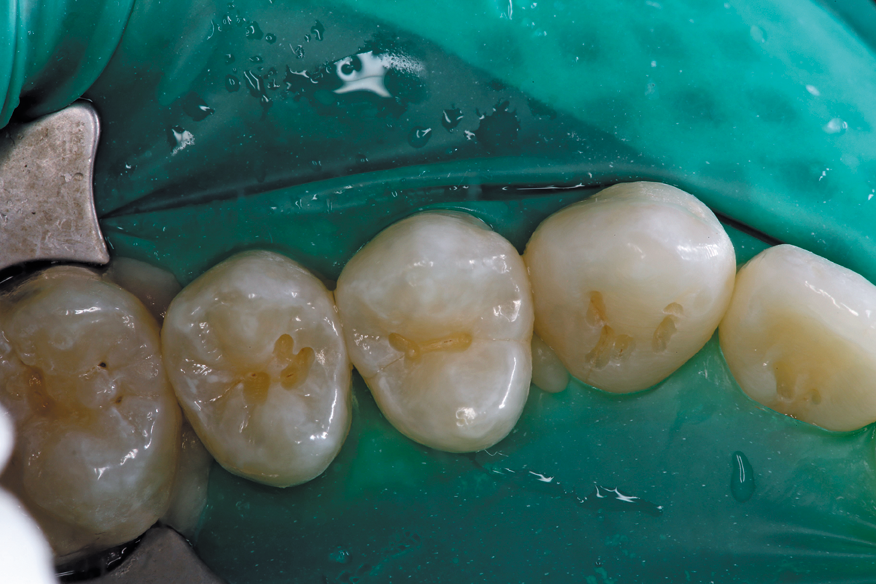

The decay is removed in both the distal pit and the mesial pit areas with no anesthesia while utilizing a 1300 FS bur.

After caries removal and proper isolation (Isolite Systems), the tooth is restored with a highly filled flowable composite (G-aenial Universal Flow, GC America Inc.) (Fig. 2).